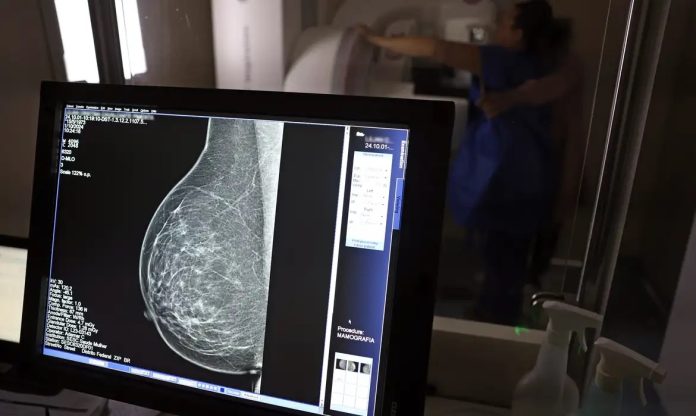

A partir de quantos anos se deve fazer a mamografia de rastreio, ou seja, como um exame de rotina, mesmo sem sintomas? Para autoridades públicas, como o Ministério da Saúde e o Instituto Nacional do Câncer (Inca), o ideal é que a mamografia seja feita a cada dois anos por todas as mulheres entre 50 e 69 anos. Algumas entidades médicas, como a Sociedade Brasileira de Mastologia (SBM), entretanto, recomendam exame anual a partir dos 40 anos.

Roberto Gil explica por que esses estudos consideram que os 50 anos são a idade certa para o início do rastreamento na população em geral: “Não estamos negando que mulheres abaixo de 50 anos tenham câncer de mama. Estamos falando que, abaixo dos 50 anos, acumulam-se outros problemas e o rastreamento populacional é menos eficiente. A mamografia é um exame de raio X, que vai ser mais efetivo na medida que a mama seja menos densa e que se tenha mais contraste na imagem, para não se confundir o parênquima normal com um nódulo. Então [antes dessa idade], aumenta muito mais a possibilidade de ter falsos positivos e ter que fazer mais exames. Posso fazer uma biópsia e ser mais difícil interpretar e levar a uma cirurgia desnecessária.”